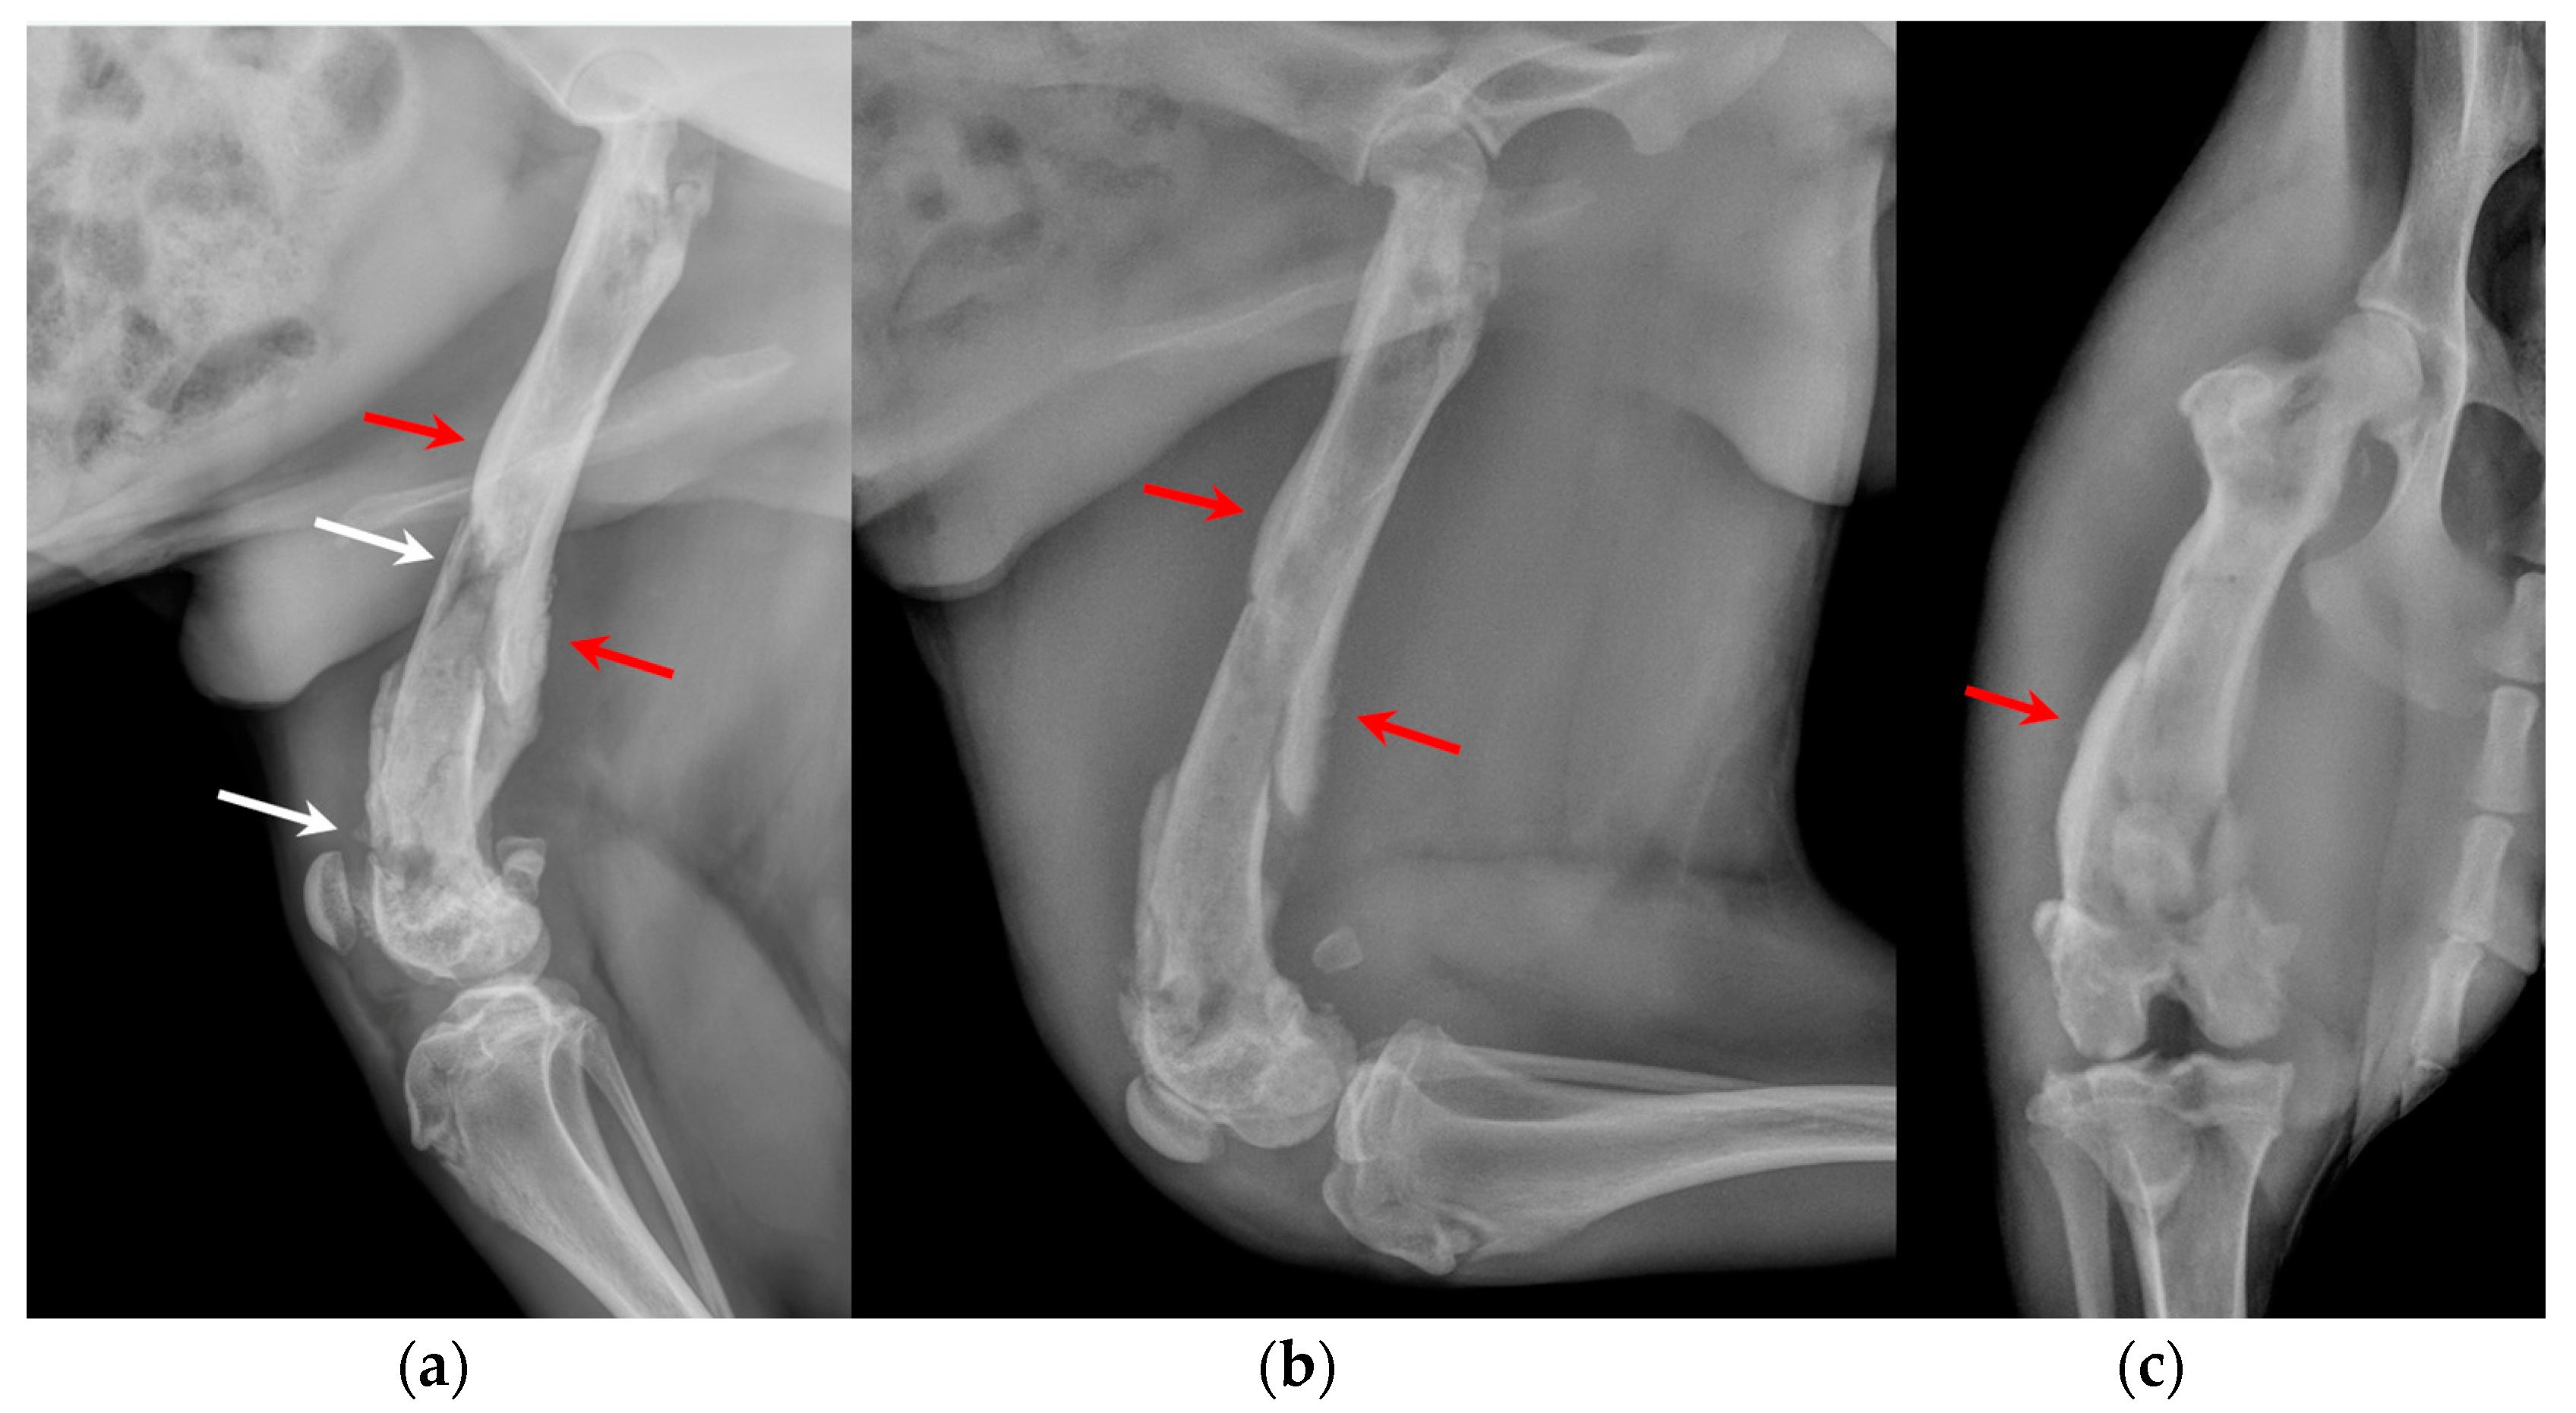

The orthopedic examination revealed no-weightbearing lameness (grade IV on a scale from 0 to IV) [19] and severe edema of the right hind limb, pain on manipulation of the right stifle, joint swelling and grade III medial patellar luxation (MPL) [20] (Figure 1, Video S1). Caudo-cranial and medio-lateral radiographic projections of the right femur, performed by reference colleagues, highlighted an extensive periosteal reaction of the diaphysis and femoral metaphysis, and a radiolucent area in the distal metaphysis (Figure 2).

Under anesthesia, a computed tomography study (CT; Somatom Emotion 16, Siemens, Munich, Germany) of the hind limbs was performed. The tomographic images revealed medullary osteolysis of the metaphysis and the distal-middle third of the femoral diaphysis. In the metaphysis and the distal third of the femoral diaphysis, a bone sequestrum was found: a wide interruption of the cranio-medial cortical profile, with involvement of the femoral trochlea, was observed with corticomedullar fragment of 4 × 1.4 cm (length × width) medially dislocated at the level of the medullary cavity; the fragment was surrounded by a large hypodense halo. Secondary MPL and widespread subcutaneous and perifascial abscess lesions were also reported (Figure 3).

Figure 2. (a) Extended medio-lateral, (b) flexed medio-lateral and (c) cranio-caudal radiographic projections of the right stifle joint and femoral diaphysis, performed by reference colleagues, highlighted an extensive periosteal reaction of the diaphysis and femoral metaphysis (red arrows) and a radiolucent area (white arrows) in the distal metaphysis.